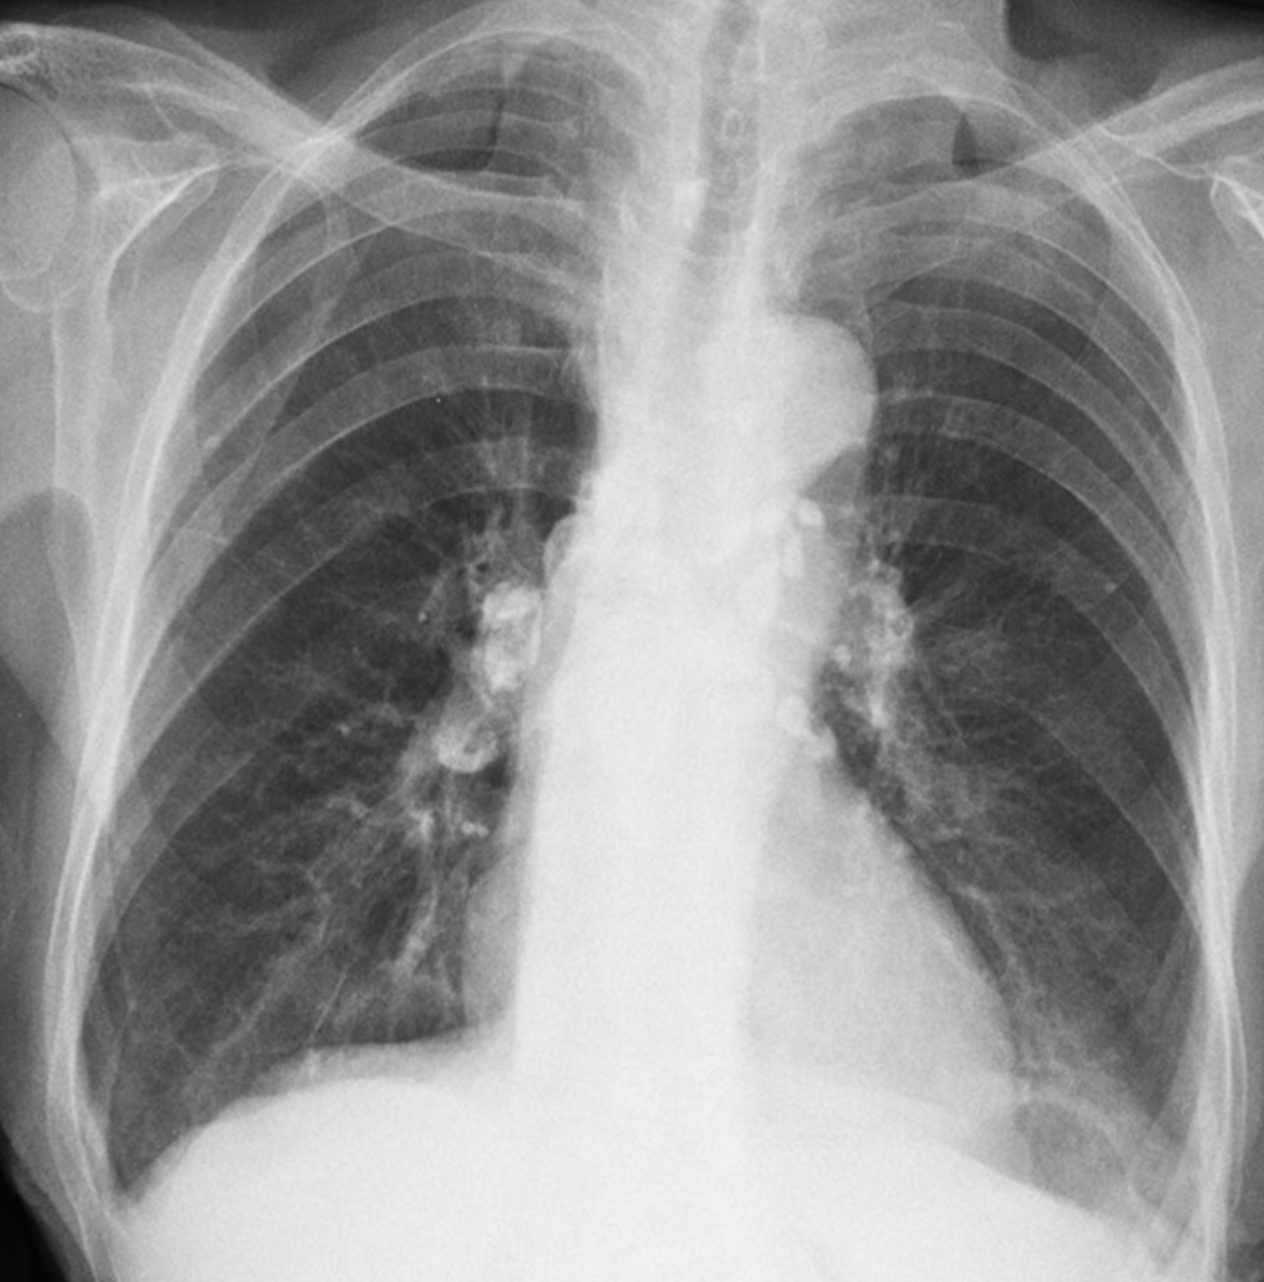

Upper zone opacities with calcified adenopathy

5